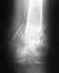

снимок 8/05/10, была на консультации в апреле по адресу Банковский,7, рекомендовали обратиться через 2 месяца ( скорее всего третья операция) , есть сомнения, исход третьей операции будет положительным.

Фото хоть и большое, но нечеткое. Ситуация не сильно тревожная, вроде что-то даже срастается. Можно обратиться на консультацию к нам в отделение (Московская, 12). Если все-таки проблема не решится в ближайшие месяцы, можно убрать пластину и установить внутрикостный стержень с блокированием.